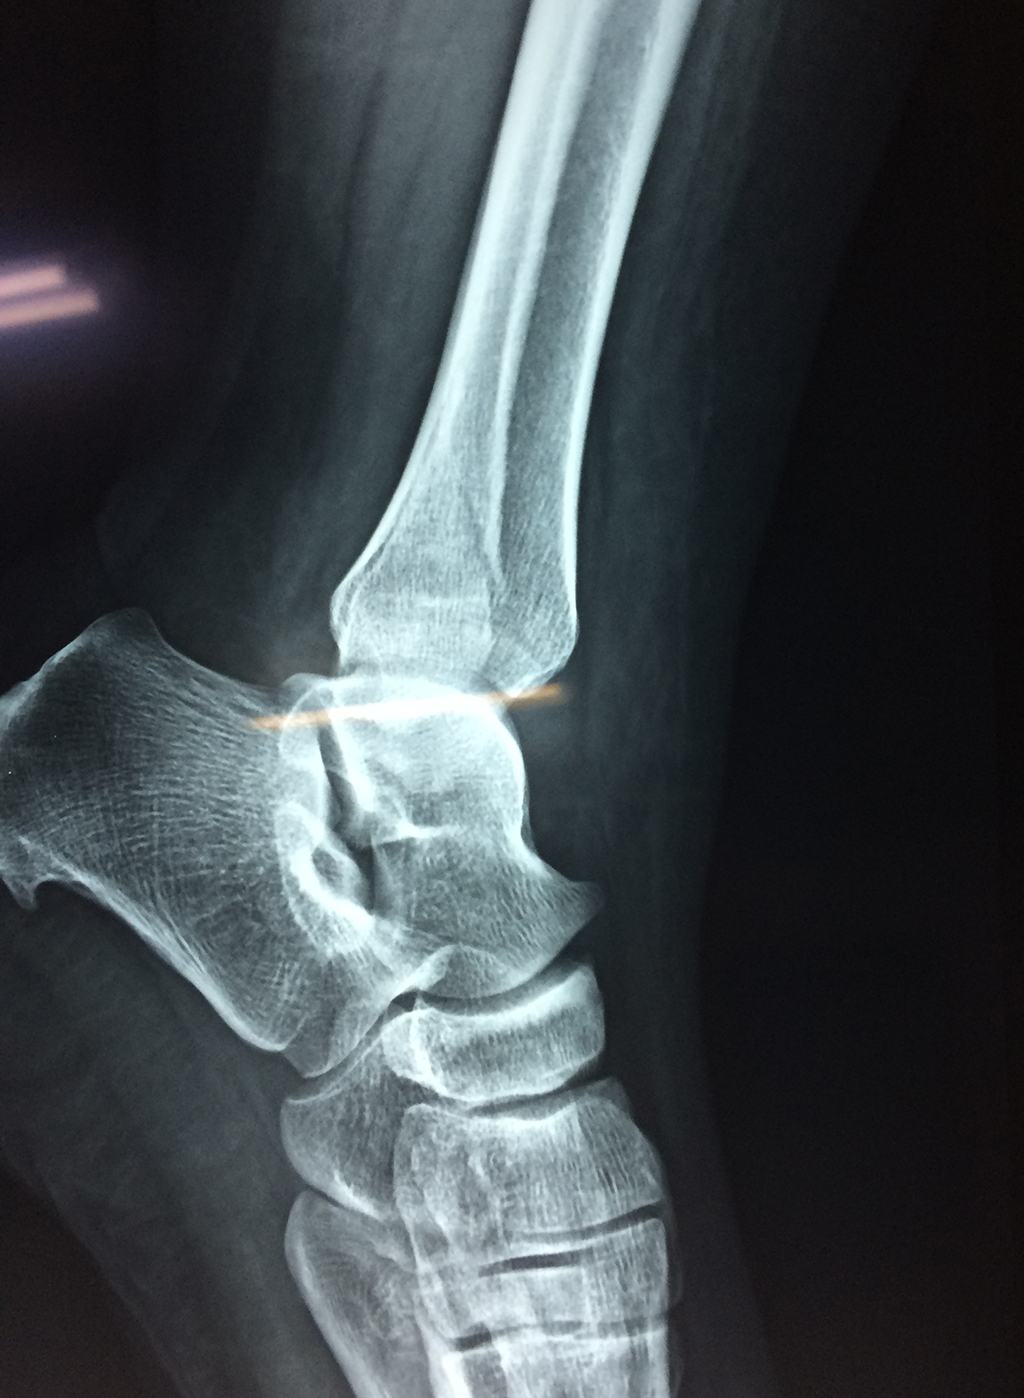

Cirugías de Peroné y Tibia

Una fractura de tobillo es la rotura de uno o más de los huesos del tobillo. Estas fracturas pueden ser:

Algunas fracturas de tobillo pueden requerir cirugía si:

- Los extremos de los huesos están desalineados entre sí (desplazados).

- La fractura se extiende hasta la articulación del tobillo (fractura intra-articular).

Cuando se necesita cirugía, es probable que esta implique el uso de clavijas de metal, tornillos o placas para sostener los huesos en su lugar mientras la fractura se consolida. Los elementos de soporte pueden ser temporales o permanentes.